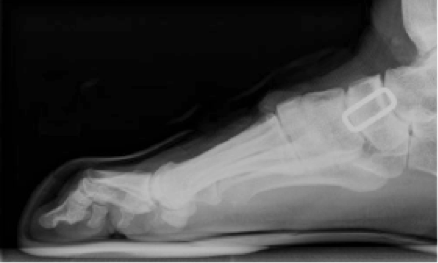

Cerca de un 50% de las lesiones agudas en escalada en roca corresponden a la extremidad inferior, debido a caídas y golpes como contusiones, fracturas, esguinces, entre otros. A nivel de lesiones crónicas, cerca del 87 a 90% de la gente que practica esta disciplina, presenta dolor o algún tipo de molestia en el pie al momento de escalar o incluso después, lo cual se debería principalmente al tipo de calzado que se utiliza. Este se caracteriza por ser muy ajustado y pequeño, lo cual facilita el apoyo sobre pequeños bordes o superficies, aumentando la fricción entre el escalador y la superficie. En comparación, las zapatillas de escalar pueden tener diferencias de tamaño entre 2 a 3 tallas, en promedio. con el calzado de uso cotidiano (Fig. 1), lo cual es ampliamente aceptado entre la comunidad, a pesar de la incomodidad que pueda provocar, con tal de mejorar el desempeño deportivo.

Figura 1. Imagen descriptiva de la diferencia entre el calzado común y el de escalada.

Este tipo de calzado cambia de manera importante la biomecánica del pie, llevando los dedos a una flexión pronunciada, aumentando el arco plantar (Fig. 2), el talón tiende a ir hacia dentro y la pierna gira externamente (Fig. 3), lo que no solo provoca tensión en la planta del pie, sino que también sobrecarga la musculatura de tobillo y dedos, teniendo consecuencias como rigidez y debilidad muscular en el mediano y largo plazo, pudiendo presentar problemas incluso en la vida diaria, como dolor e incomodidad al caminar.

FIgura 2. Radiografía lateral de un pie dentro de una zapatilla de escalada.